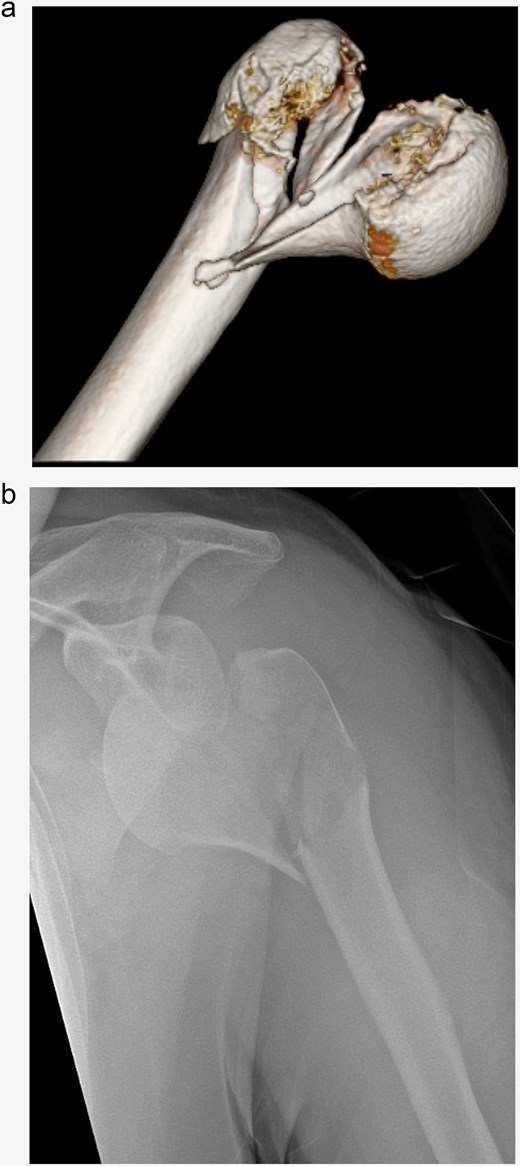

Open reduction and internal fixation with a locking plate was performed the following day. Following the deltopectoral approach, a reduction of the antero-inferiorly dislocated fragment through Kocher maneuvers and traction on the head fragment using a pointed reduction forceps were achieved. Subsequently, the head-split component was addressed by securing it with Ethibond sutures within the rotator cuff. The remaining fragments were then reduced and stabilized using a 5-hole anatomical locking compression plate along with a total of eight head and seven shaft screws, all performed under radiological guidance (Fig. 2).

The initial postoperative therapy proceeded without complications and the patient was able to perform initial pendulum exercises under physiotherapeutically guidance. In the postoperative radiographic assessment of the fracture fragments exhibited an anatomically aligned position. However, it also showed a slight widening of the subacromial space. Antiepileptic therapy was again reviewed and adjusted in consultation with a neurologist to minimize the risk of future seizures.